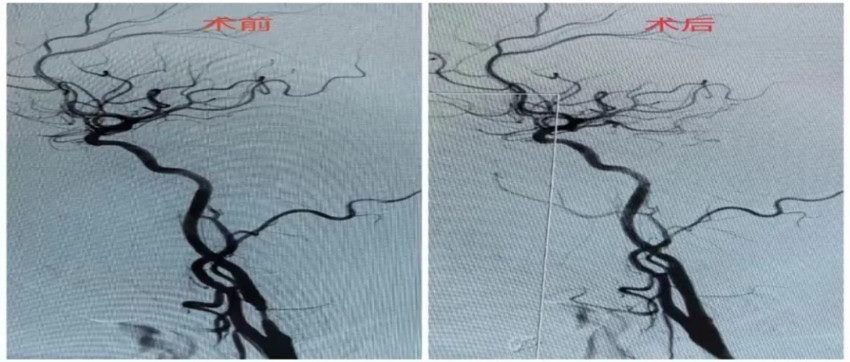

▲ 颈动脉支架植入术前后DSA图像